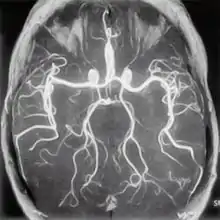

МР-ангиография

Магнитно-резонансная ангиография (МРА) — метод получения изображения просвета сосудов при помощи магнитно-резонансного томографа. Метод позволяет оценивать как анатомические, так и функциональные особенности кровотока. МРА основана на отличии сигнала от перемещающихся протонов (крови) от окружающих неподвижных тканей, что позволяет получать изображения сосудов без использования каких-либо контрастных средств — бесконтрастная ангиография (фазово-контрастная МРА и время-пролетная МРА). Для получения более чёткого изображения применяются особые контрастные вещества на основе парамагнетиков (гадолиний).